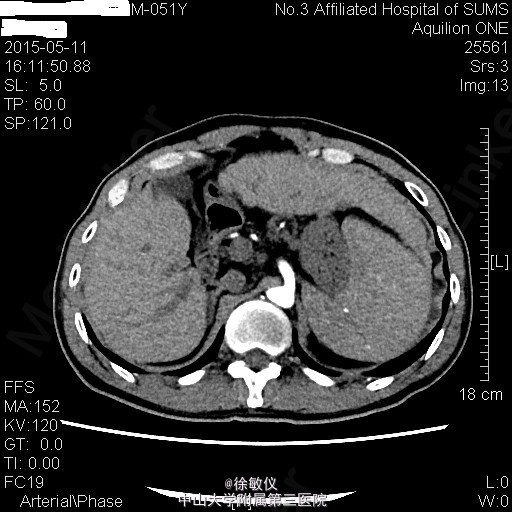

查体:生命体征平稳。皮肤无黄染,巩膜轻度黄染,未见肝掌、蜘蛛痣,未见瘀点或瘀斑。心肺查体无特殊。腹部外形平坦,未见腹壁静脉曲张,腹软,无压痛、反跳痛,肝肋下未触及,Murphy(-)。脾肋下6cm,质软,边界光滑,无压痛。 辅查:血常规:WBC 2.03x10E9/L,Hb 106g/L,PLT 51x10E9/L。 生化:白蛋白34.6g/L,转氨酶正常。 凝血:凝血酶原时间17.2sec,凝血酶原活动度61%。 全腹螺旋CT平扫+增强:1、肝硬化,门脉高压,脾大,食道下段胃底静脉曲张,附脐静脉开放,脾静脉增粗、迂曲。2、慢性胆囊炎。3、前列腺增生。4、全腹CTA:右侧副肾动脉形成。5、左肺下叶少许慢性炎症。